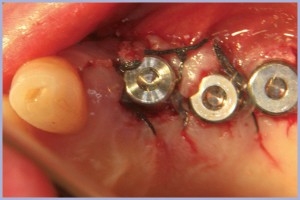

In una seduta successiva si inseriscono 3 impianti: in sede 24 (ø 4.1 L 12 mm), 25 (ø 4,1 L 10 mm) e 26 (ø 4,8 L 8 mm) aprendo un lembo, apponendo osso sintetico in zona vestibolare per la scarsità di osso e inserendo comunque tappi di guarigione standard vista la buona stabilità primaria (figg. 13-15).

- Fig. 13

- Fig. 14

- Fig. 15